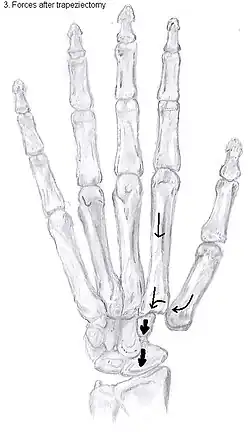

Trapeziectomy

During trapeziectomy,[30] the trapezium bone is removed without any further surgical adjustments. The trapezium bone is removed through an approximately three centimeter long incision along the lateral side of the thumb. To preserve surrounding structures, the trapezium bone is removed "by splitting" it into pieces.

An empty gap is left by the trapeziectomy and the wound is closed with sutures. Despite this gap, no significant changes in function of the thumb are reported.[27] After the surgery, the thumb will be immobilized with a cast.

Trapeziectomy with tendon interposition

Some physicians still believe that it is better to fill the gap left by the trapeziectomy. They assume that filling the gap with a part of a tendon is preferable in terms of function, stability and position of the thumb. This is based on the assumption that interposition can help maintain the space between the metacarpal and the scaphoid, which will improve comfort and capability. Neither of these assumptions is supported by experimental evidence.

During trapeziectomy with TI, a longitudinal strip of the palmaris longus tendon is collected. [31] If this tendon is absent (which is the case in 13% of the population), half of the flexor carpi radialis tendon (FCR) can be used.

The tendon is then formed into a circular shape and placed in the gap, where it is stabilized by sutures.[12]

Trapeziectomy with ligament reconstruction

Another technique is used to reconstruct the volar beak ligament after trapeziectomy. The rationale is that ligament reconstruction(LR) helps maintain the gap between the metacarpal and the scaphoid, and that a larger gap is associated with greater comfort and capability.[32] Again these possibilities are not supported by experimental evidence.

During this procedure the anterior oblique ligament is reconstructed using the FCR tendon. There is a wide variety in techniques to perform this LR, but they all have a similar goal.

Trapeziectomy with LRTI

Some physicians believe that combining LR with TI will help maintain gap between the metacarpal and the scaphoid.[33] And that doing so will improve comfort and capability. Keep in mind that these aspects of the rationale are not supported by experimental evidence. The evidence suggests that all of these procedures have comparable long-term results.